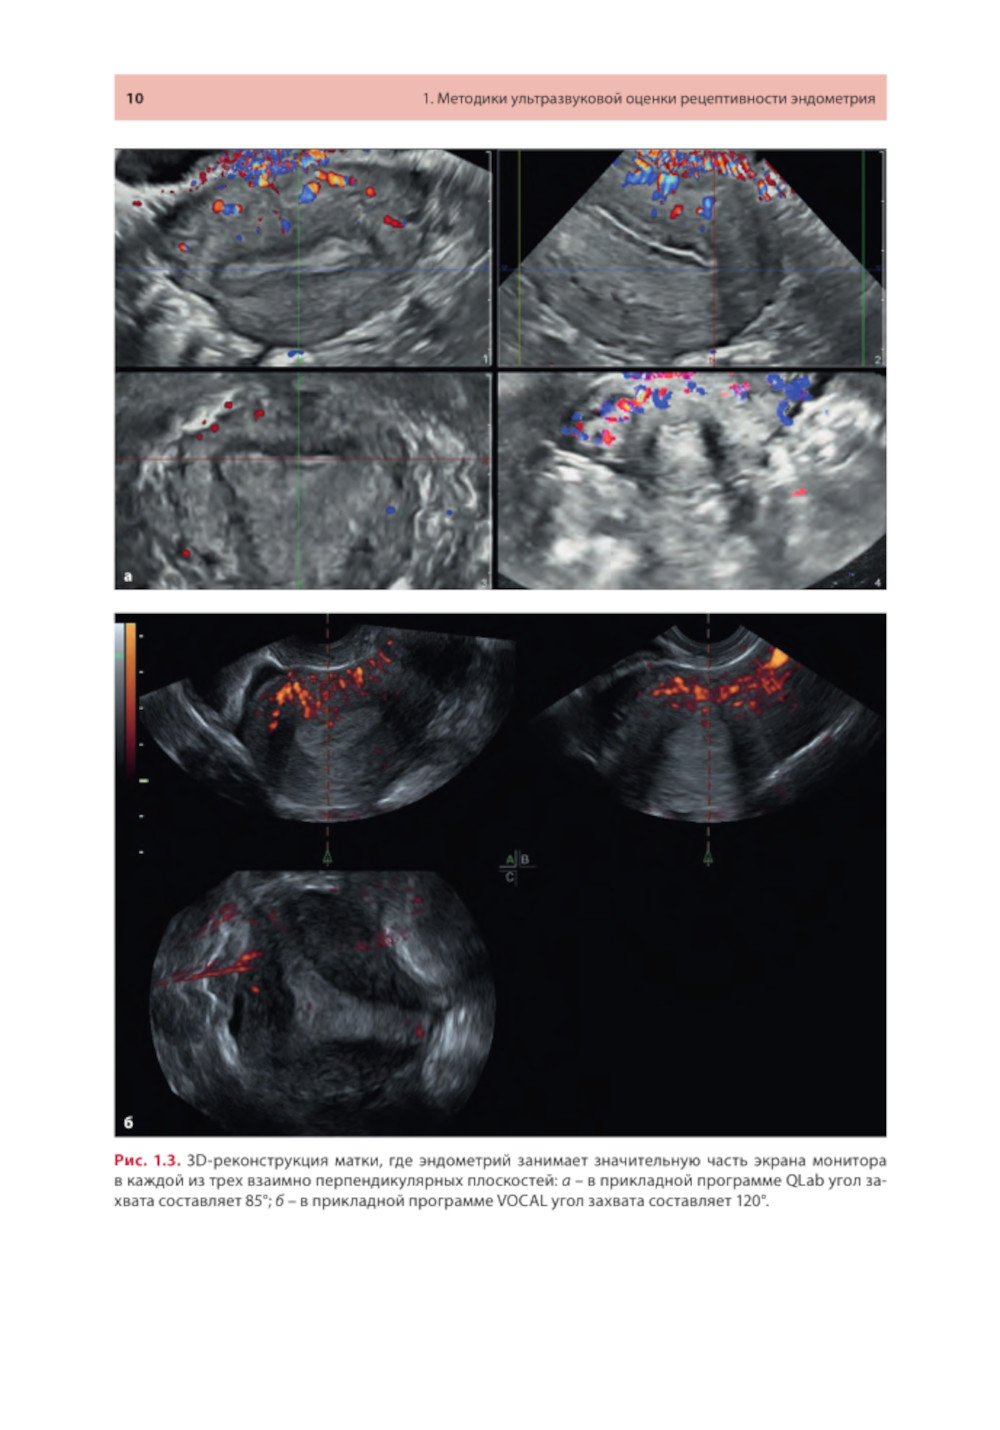

Методические рекомендации освещают современное состояние проблемы ультразвуковой оценки рецептивности эндометрия от общепринятых маркеров до малоизученных, в том числе перспективных, направлений. Описаны ультразвуковые методики, позволяющие оценивать признаки рецептивности в 2D- и 3D-режимах с акцентом на ошибках, которые влияют на интерпретацию результатов. Представлены различные шкалы комплексного анализа. Утверждено в качестве методических рекомендаций для проведения циклов тематического усовершенствования «Ультразвуковая диагностика в гинекологии», общего усовершенствования, ординаторов и аспирантов, проходящих обучение по направлению «Ультразвуковая диагностика, акушерство и гинекология, репродуктология». Протокол Ученого совета ФНМО МИ ФГАОУ ВО РУДН №5 от 16.05.2023.| Издательство | МЕДпресс-информ |